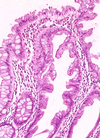

Histology: Yellow-white mucosal plaques or pseudomembranes; may resemble polyps or aphthoid ulcers of Crohn’s disease. Mucopurulent exudate erupts out of crypts to form a mushroom-like cloud with a linear configuration of karyorrhectic debris and neutrophils that adheres to surface.